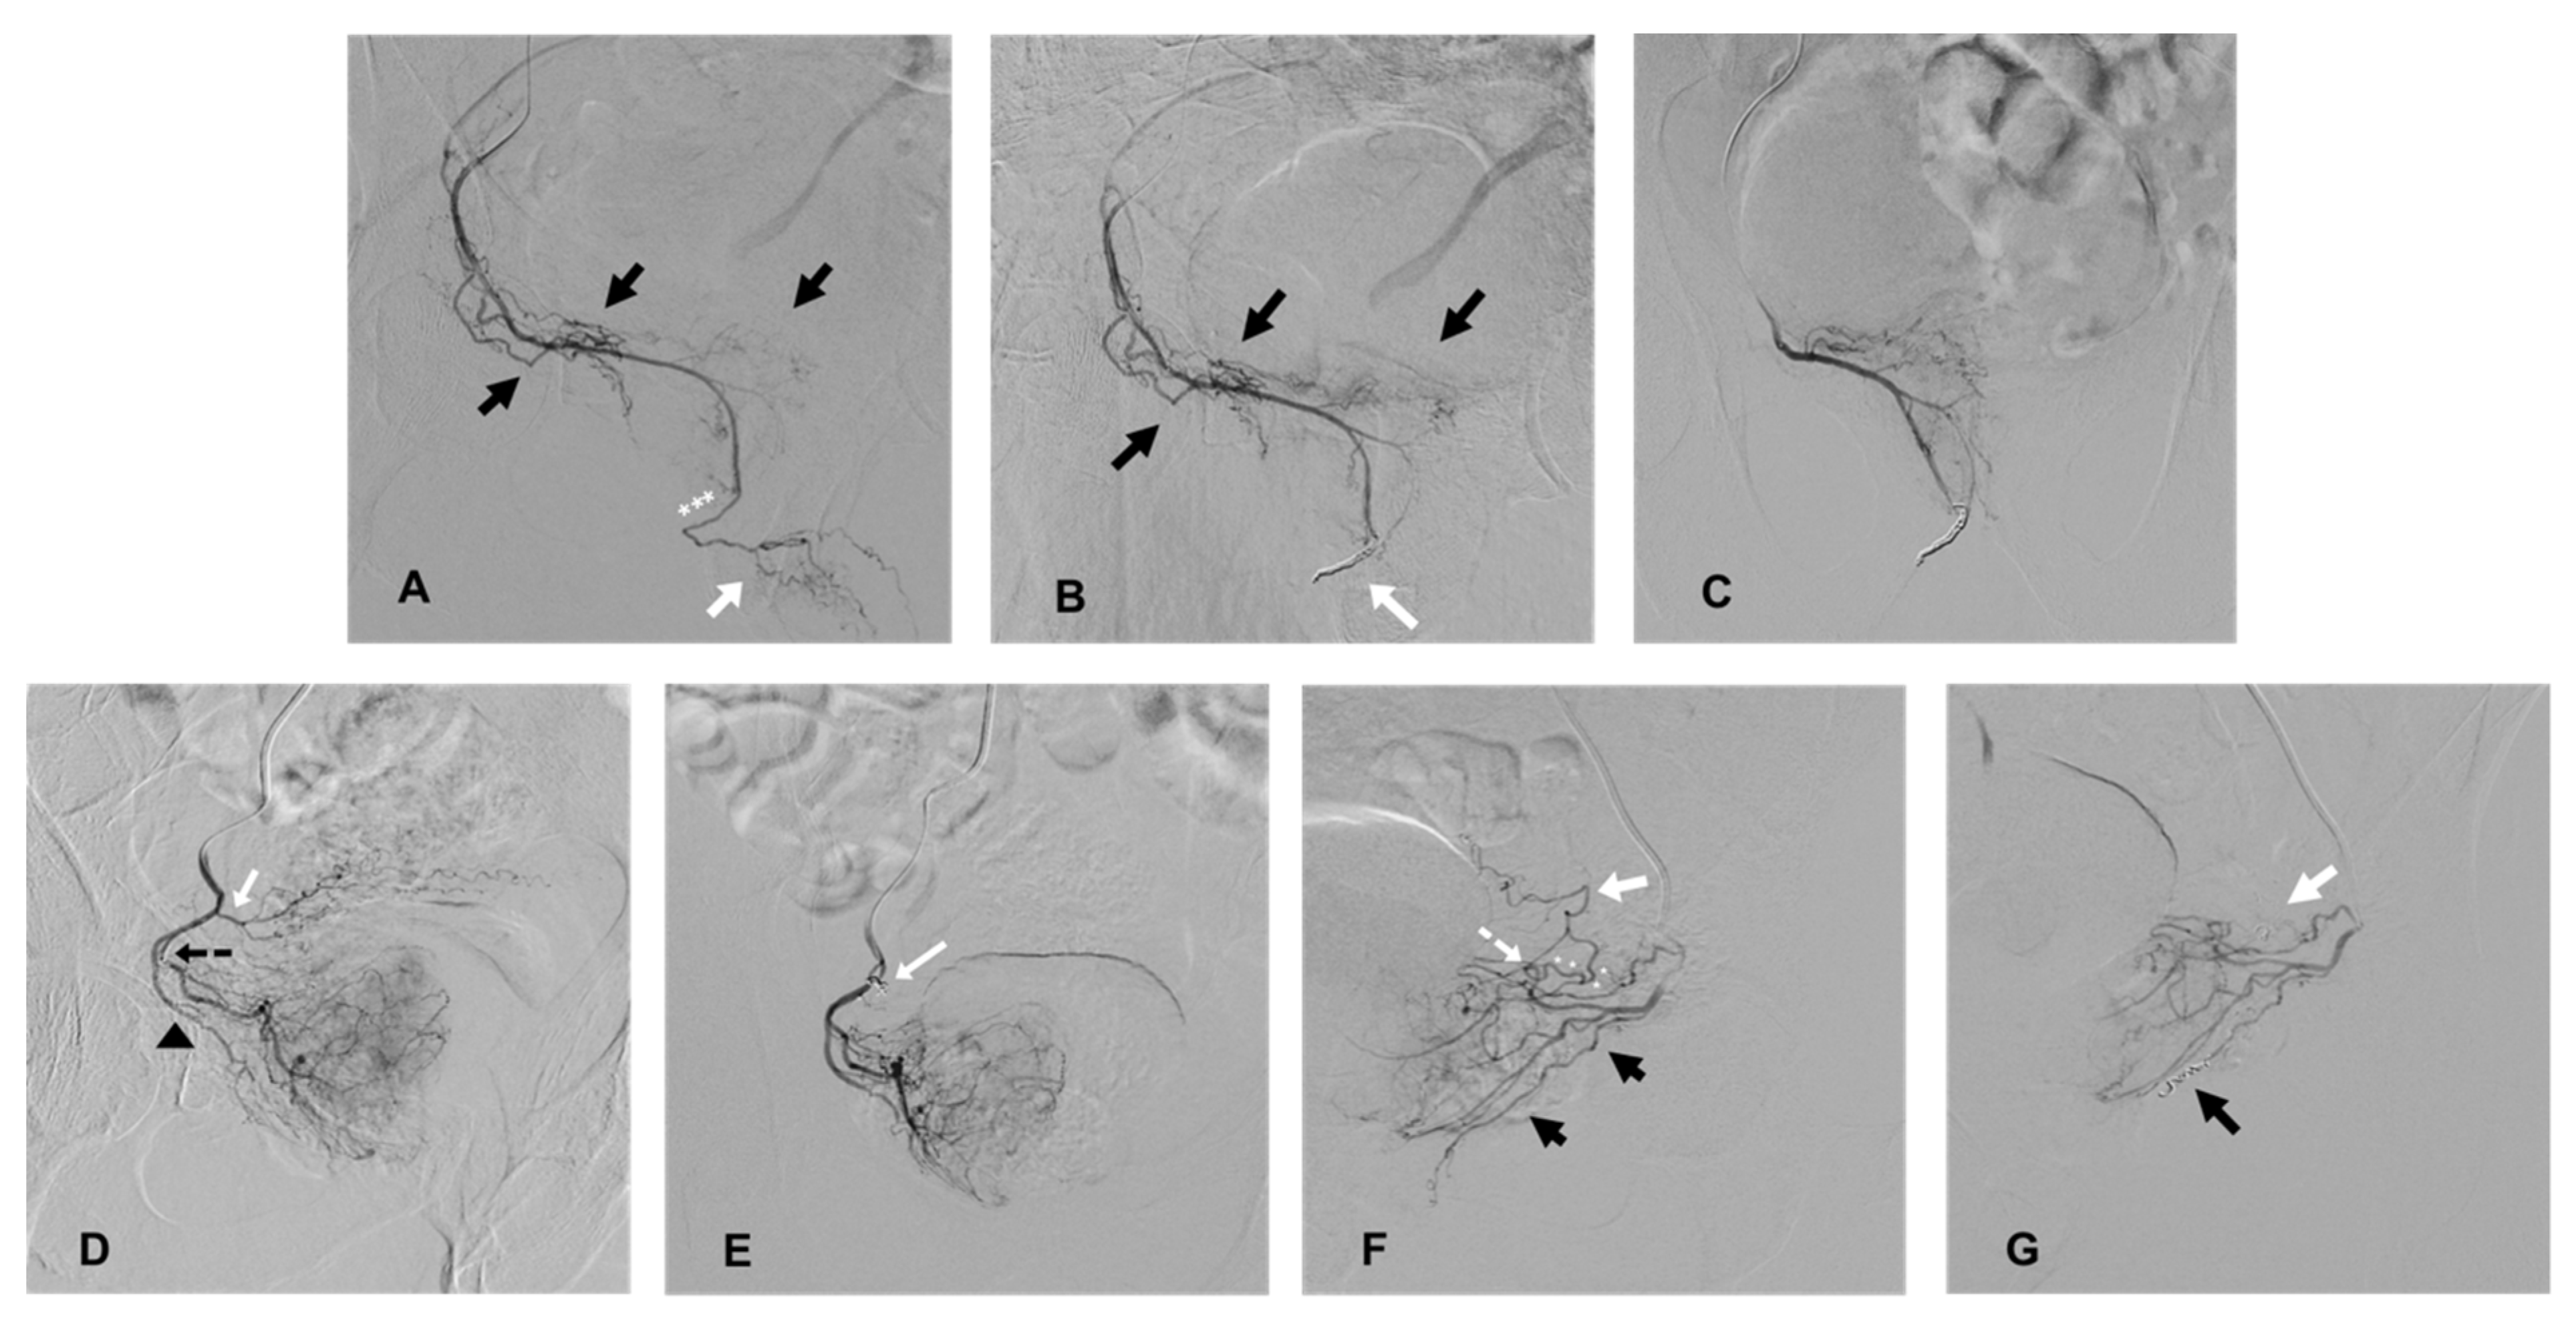

Figure 1.

Cases of coil protection of extra-prostatic supplies during PAE and prior to microparticle delivery for safe embolization. (A–C) present a case of coil protection of a pattern B prostatic artery (PA). (A): selective angiography of the right PA on an ipsilateral oblique view, originating from a right accessory internal pudendal artery (APA). Penile arteries are visible at the end of the APA (white arrow) and distally to the prostatic arterial branches (black arrows); the penile bed should be protected from microparticle non-target prostatic embolization (the elective location of occlusion is marked with white asterisks). (B): repeat angiography on ipsilateral oblique view, prior to microparticle delivery, and after a 2 and 3 mm diameter detachable microcoil insertion (white arrow). Penile supply is occluded (penile arteries are no longer opacified) and prostatic vessels are still patent (black arrows). (C): repeat angiography on anteroposterior (AP) view prior to prostatic embolization for confirmation of a full uptake of the right hemi prostate. Penile supply is still occluded. (D,E) present a case of occlusion of an accessory inferior vesical artery (AIVA). (D): selective angiography of the right PA on ipsilateral oblique view. The tip of the microcatheter is inserted in the medial branch of the PA (marked by a black, dotted arrow) and the lateral prostatic branch is marked by a black arrow head. Early reflux is observed in an ipsilateral AIVA (white arrow) originating from the PA, confirming the risk of non-target embolization. (E): repeat angiography on AP view prior to PAE and after the insertion of a 2 mm detachable coil in the AIVA (white arrow). The vesical supply is no longer visible and there is a full uptake of the right hemi prostate. (F,G) present a case of occlusion of rectal and vesical supplies. (F): selective angiography on ipsilateral oblique view of a left prostatic artery, which carries a common trunk with a rectal artery (black arrows), described as pattern C1. There is an associated anastomosis (arterial loop marked by a white, dotted arrow) between the PA and left inferior vesical artery (IVA, white arrow), which needs to be occluded prior to microparticle delivery (elective location marked by white asterisks). (G): repeat angiography on oblique view prior to PAE and after the insertion of 2 mm detachable micro coils in the anastomosis to the IVA (white arrow) and in the rectal artery (black arrow), confirming the occlusion of vesical and rectal supplies.